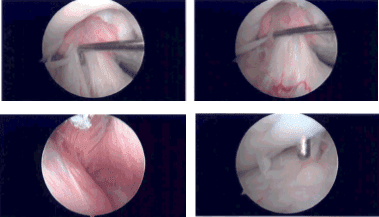

The medical entry was made with the use of a spinal needle and blade. Examination of the medial tibiofemoral compartment showed intact cartilage and meniscus. Examination of the intercondylar notch showed intact, but frayed and degenerated ACL. There was a tear flap from the anterior margin of the lateral meniscus.

A shaver was used to debride the meniscus and do the meniscectomy. Examination of the rest of the lateral tibiofemoral compartment showed intact cartilage of meniscus. Examination of the patellofemoral compartment showed grade 1 changes over the trochlea and patella.

There was a grade 2 osteochondral lesion of the patella, which was debrided with the use of a shaver. The rest of the knee was intact. The knee was thoroughly irrigated and drained. All the pictures were saved.

Intraoperative Arthroscopy Images